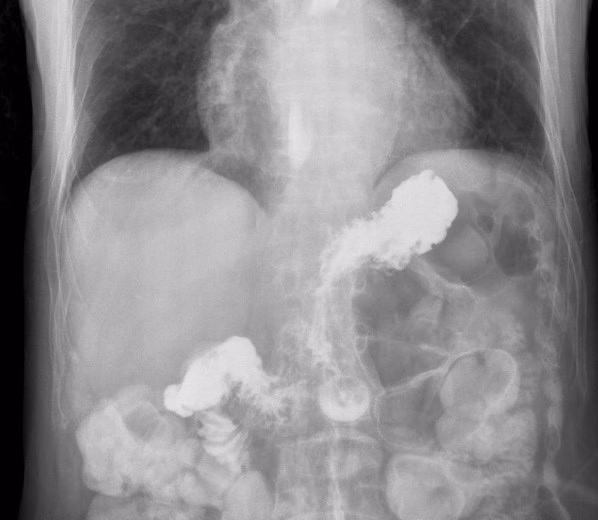

GERD is thought to arise because of a condition known as hiatal hernia. Hiatal hernia occurs as part of the stomach pushes upward through a small opening in the diaphragm that is meant for the passing of food on its way to the stomach. The LES is a ring of muscle located between the esophagus and stomach. GERD causes people to suffer from either heartburn or acid indigestion.

A hiatal hernia is thought to weaken the LES, therefore increasing the risk for gastroesophageal reflux. Increased pressure in the abdomen due to coughing, vomiting, straining, or sudden physical exertion can lead to hiatal hernia. Other conditions that can potentially lead to hiatal hernia are obesity and pregnancy. Hiatal hernias are known to affect people in their later years, but they can occur in people of all ages

Hiatal hernias are typically fine when left untreated, but treatment becomes necessary if the hernia is in danger of becoming twisted in a way that cuts of blood supply or is furthered by severe GERD or inflammation of the esophagitis. Treatment of hiatal hernias requires a surgical procedure to reduce the size of the hernia or to prevent strangulation.